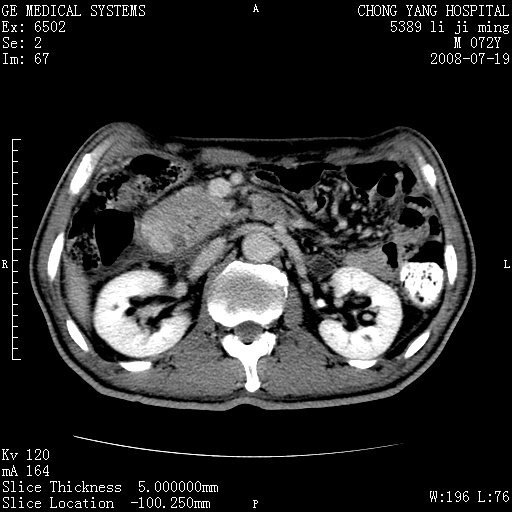

以下是引用zjzjr在2008-7-19 20:57:00的发言:[br]胰头增大,边缘模糊,周围可见渗出影,右侧肾前筋膜增厚.支持胰腺炎.

以下是引用yangyudong333在2008-7-20 6:56:00的发言:[br]胰腺增大尤以胰头明显,边缘模糊,周围可见渗出影,右侧肾前筋膜增厚,肠管於涨.支持胰腺炎

以下是引用不学无术在2008-7-19 23:15:00的发言:[br]胰腺增大尤以胰头明显,边缘模糊,周围可见渗出影,右侧肾前筋膜增厚,肠管於涨.支持胰腺炎